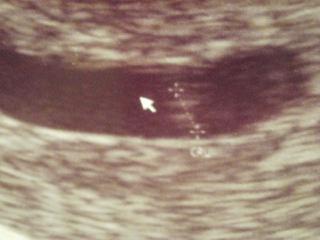

ahojka holky 🙂 tak jsem 2 hodiny čekala v čekárně, ale ten zážitek z toho pulzujícího "srdíčka" stálo za to 🙂 ukápla mi slzička a jsem štastná strašně moc 🙂 jsme ale menší než podle ms, doktor říkal, že mu to utz neukázal, ale že to vidí tak o týden menší, takže si myslim že jsem tak 6/7 týdne, nevim , embryjko má 3,36mm a v pátek jdu na krev a načůrat a 19.12 do první těhotenské poradny, tam mi prý poví víc v kolikátem jsem týdnu 🙂 je to nádhernej pocit 🙂 🙂

@barbulinka1 jéééééé, to je krásná fotečka 🙂.. Já jdu zítra, tak na nás taky moc mysli 🙂. Podle ms jsem 6+6, podle ovu asi 4+2. Chtěla bych už taky slyšet srdíčko, ale myslím, že budeme ještě malý.. Hele na první KO dělá jen UTZ nebo i prohlídku "zevnitř"? 🙂

@petinkas Děkuju 🙂 🙂 já už jsem na jednom byla cca ve 4. týdnu a byla tam jenom 3mm gestační váček, ted už je o dost větší a je tam i embryjko 🙂 a já si myslím, že jsem cca 6+5 nebo tak nějak dneska a poprvé nevím mě dělal rovnou i stěry a preventivku ale dneska mi jen zkontroloval dělohu a řekl, že je teda pěkně narostlá 😀 a pak hned ultravuk 🙂 ale myslim si, že te zkontroluje zevnitř a pak vnitřní vaginální ultrazvuk přes bříško by ještě nic neviděl si myslim 🙂